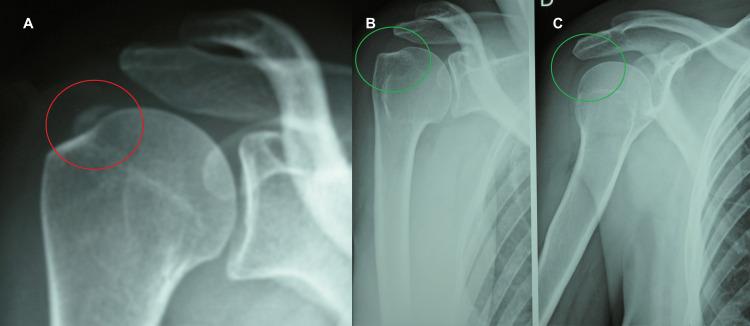

Calcific tendinitis of the shoulder (CTS) is one of the pathological conditions that most often affects the shoulder and consists of a calcium deposit that settles within the tendon tissue of the rotator cuff. The scientific literature has long highlighted the impact of anxiety, stress, and depression on CTS. The goal of this case report is to highlight how the emotional state of patients and their neuro-psychomotor behavior induce a state of constant muscular tension which, through the physical phenomenon of piezoelectricity, causes calcium salts to precipitate and form calcifications. Therefore, stress, anxiety, and depression are likely factors underlying the etiopathogenesis of CTS. Consistent with this interpretation, this report presents five cases of CTS treated with three specific neurobiological stimulation treatments using the radioelectric asymmetric conveyer (REAC) technology, which has demonstrated its effectiveness on alterations in postural attitude intended as neuro-psychomotor behavior, anxiety, stress, and depression, as well as on autonomic and metabolic alterations of the tissues at a local level. The results presented suggest that this approach may be useful in the treatment and prevention of CTS.

肩部钙化性肌腱炎(CTS)是最常影响肩部的病理状况之一,由沉积在肩袖肌腱组织内的钙沉积物组成。科学文献长期以来一直强调焦虑、压力和抑郁对CTS的影响。本病例报告的目的是强调患者的情绪状态及其神经心理运动行为如何诱发持续的肌肉紧张状态,这种状态通过压电物理现象导致钙盐沉淀并形成钙化。因此,压力、焦虑和抑郁可能是CTS发病机制的潜在因素。与这种解释一致,本报告介绍了五例CTS患者,采用三种特定的神经生物学刺激疗法进行治疗,使用无线电不对称输送器(REAC)技术,该技术已证明其对作为神经心理运动行为的姿势态度改变、焦虑、压力和抑郁以及局部组织的自主和代谢改变有效。所呈现的结果表明,这种方法可能对CTS的治疗和预防有用。